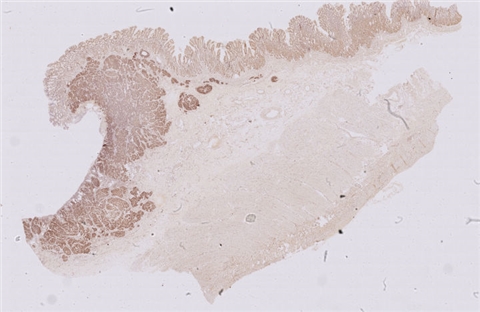

性别:       年龄:41

患者详情: 患者诉1天前无明显诱因出现脐周腹痛,持续性钝痛,不向远处部位放射,进食后感恶心,无呕吐,无发热、腹泻等不适,后腹痛逐渐转移至右下腹,遂来我院诊治,门诊拟“急性阑尾炎”收住入院,临床拟急性阑尾炎行手术切除。

大体所见: 阑尾一条,长4.0厘米,管径0.7-0.9厘米,浆膜面灰白色、附有脓苔。

免疫组化: 肿瘤细胞:CDX-2(+)、CEA(+)、CK(+)、ECD(+); P53(+),SATB-2(+),CD56(少量+),CgA(-),syn(+)

医院: 赣州市人民医院